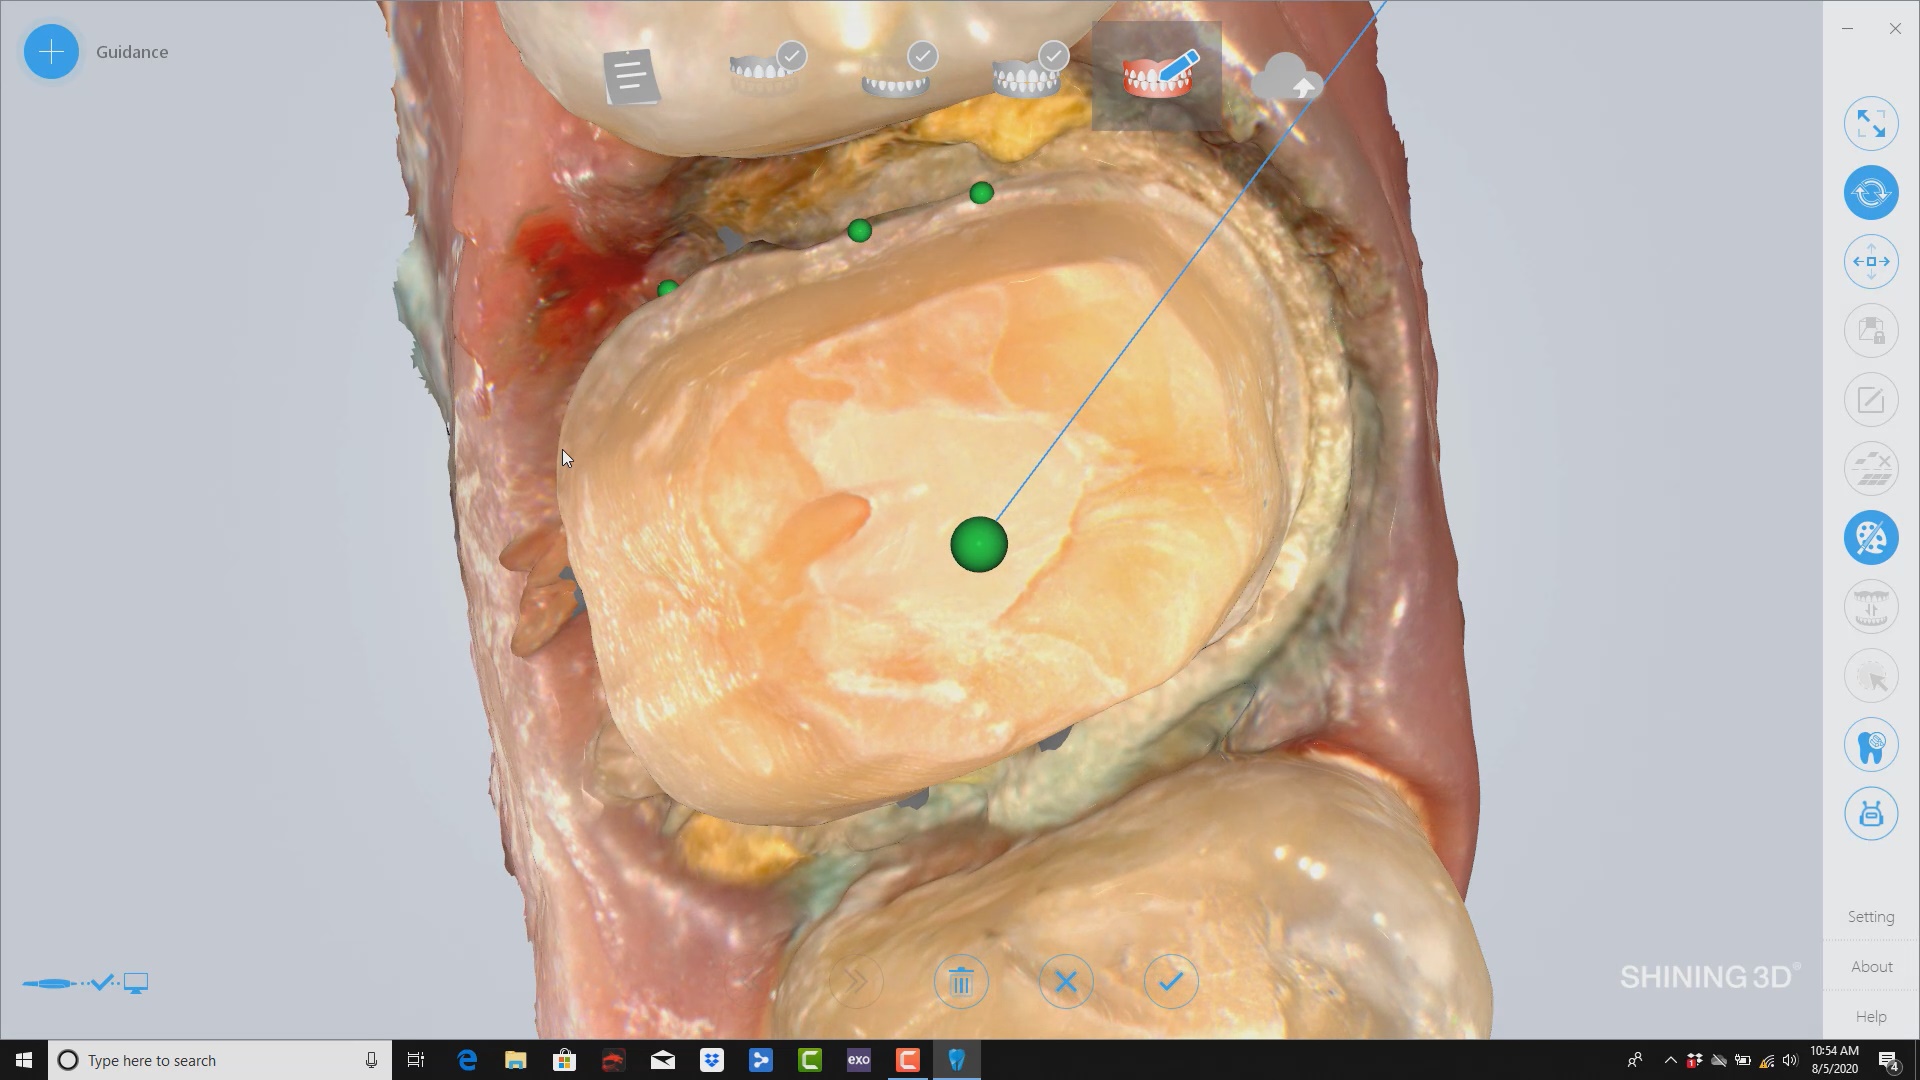

Shining3d has a projector and a single camera that takes photos of the surfaces it is scanning. at first, you may think this is a shortcoming, but in many ways, […]